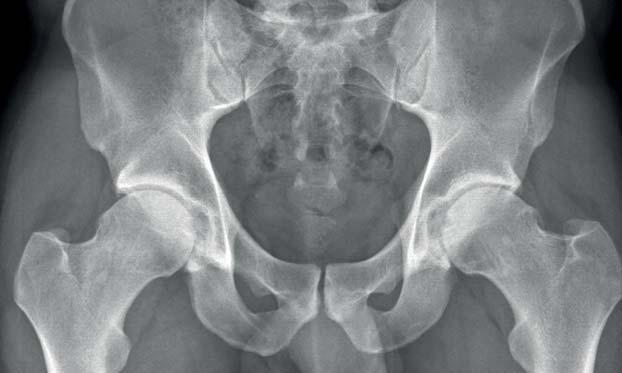

Die Diagnosemethode erster Wahl bei Verdacht auf Verletzungen oder Anomalien an Knochen ist das Röntgenbild. Auch ein Knorpelabbau lässt sich durch ein Röntgenbild im Stehen diagnostizieren.